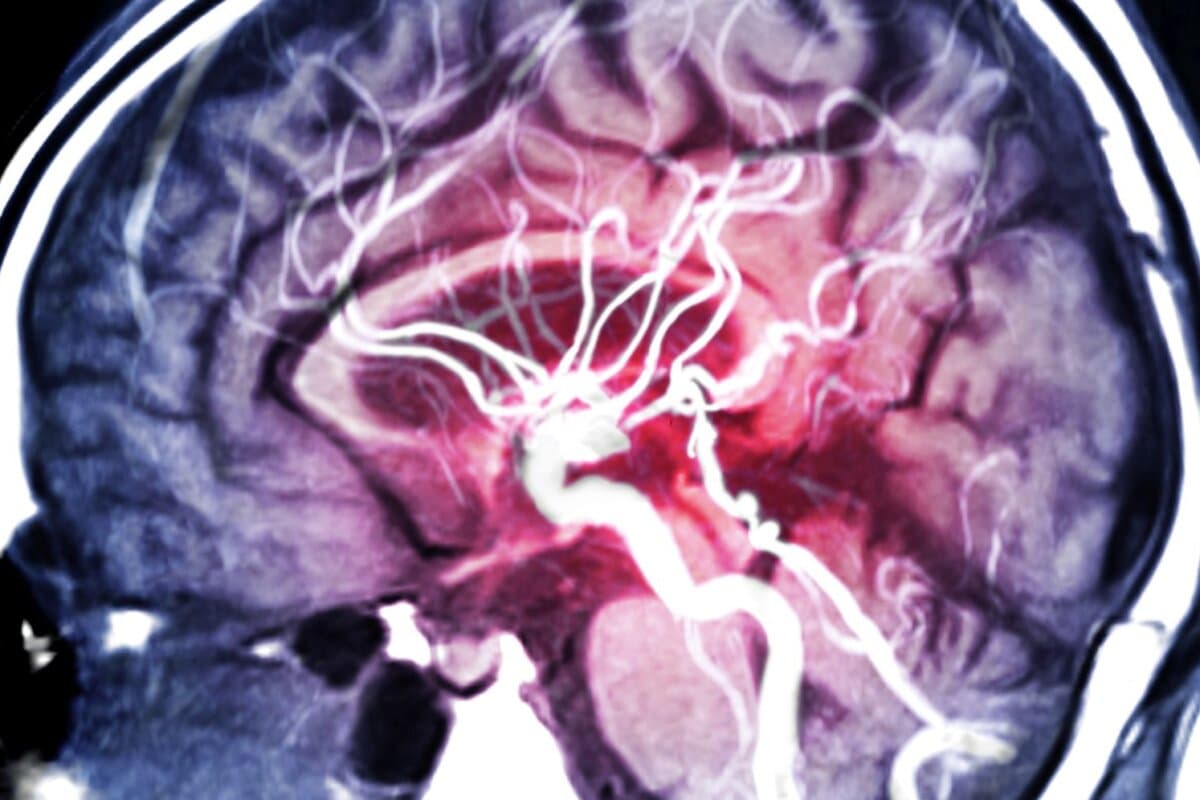

La vascularite cérébrale primaire peut provoquer de nombreux syndromes neurologiques et est souvent confondue avec des maladies qui sont plus fréquentes. Attendre peut être fatal car seul un traitement précoce par corticoïdes peut prévenir contre des lésions irréversibles.

La vascularite cérébrale primaire, également appelé angiite primaire, se limite au cerveau et à la moelle épinière. Elle touche aussi bien les hommes que les femmes, peut survenir à tout âge et est associée à une mortalité de 8 à 23 %. Malgré le traitement, environ un quart des patients restent sévèrement handicapés, selon l’équipe dirigée par le Dr Carlo Salvarani, Mayo Clinic (1).

L’incidence est d’environ 2,4 cas par million de personnes-années, et on distingue deux types d’atteinte des petits ou moyens à gros vaisseaux. Le plus souvent, la vascularite se manifeste par l’apparition soudaine de déficits neurologiques faisant penser à un accident ischémique transitoire ou à un accident vasculaire cérébral, y compris l’aphasie, l’ataxie et les déficits du champ visuel. Les céphalées, les déficits cognitifs progressifs et les signes aigus et subaigus d’encéphalopathie sont également plus fréquents.